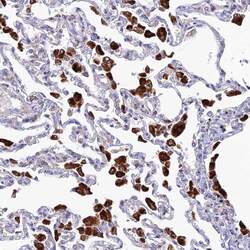

- Main image

- Experimental details

- Immunohistochemical analysis of SPNS1 in human lung using SPNS1 Polyclonal Antibody (Product # PA5-59813) shows strong granular cytoplasmic positivity in macrophages.